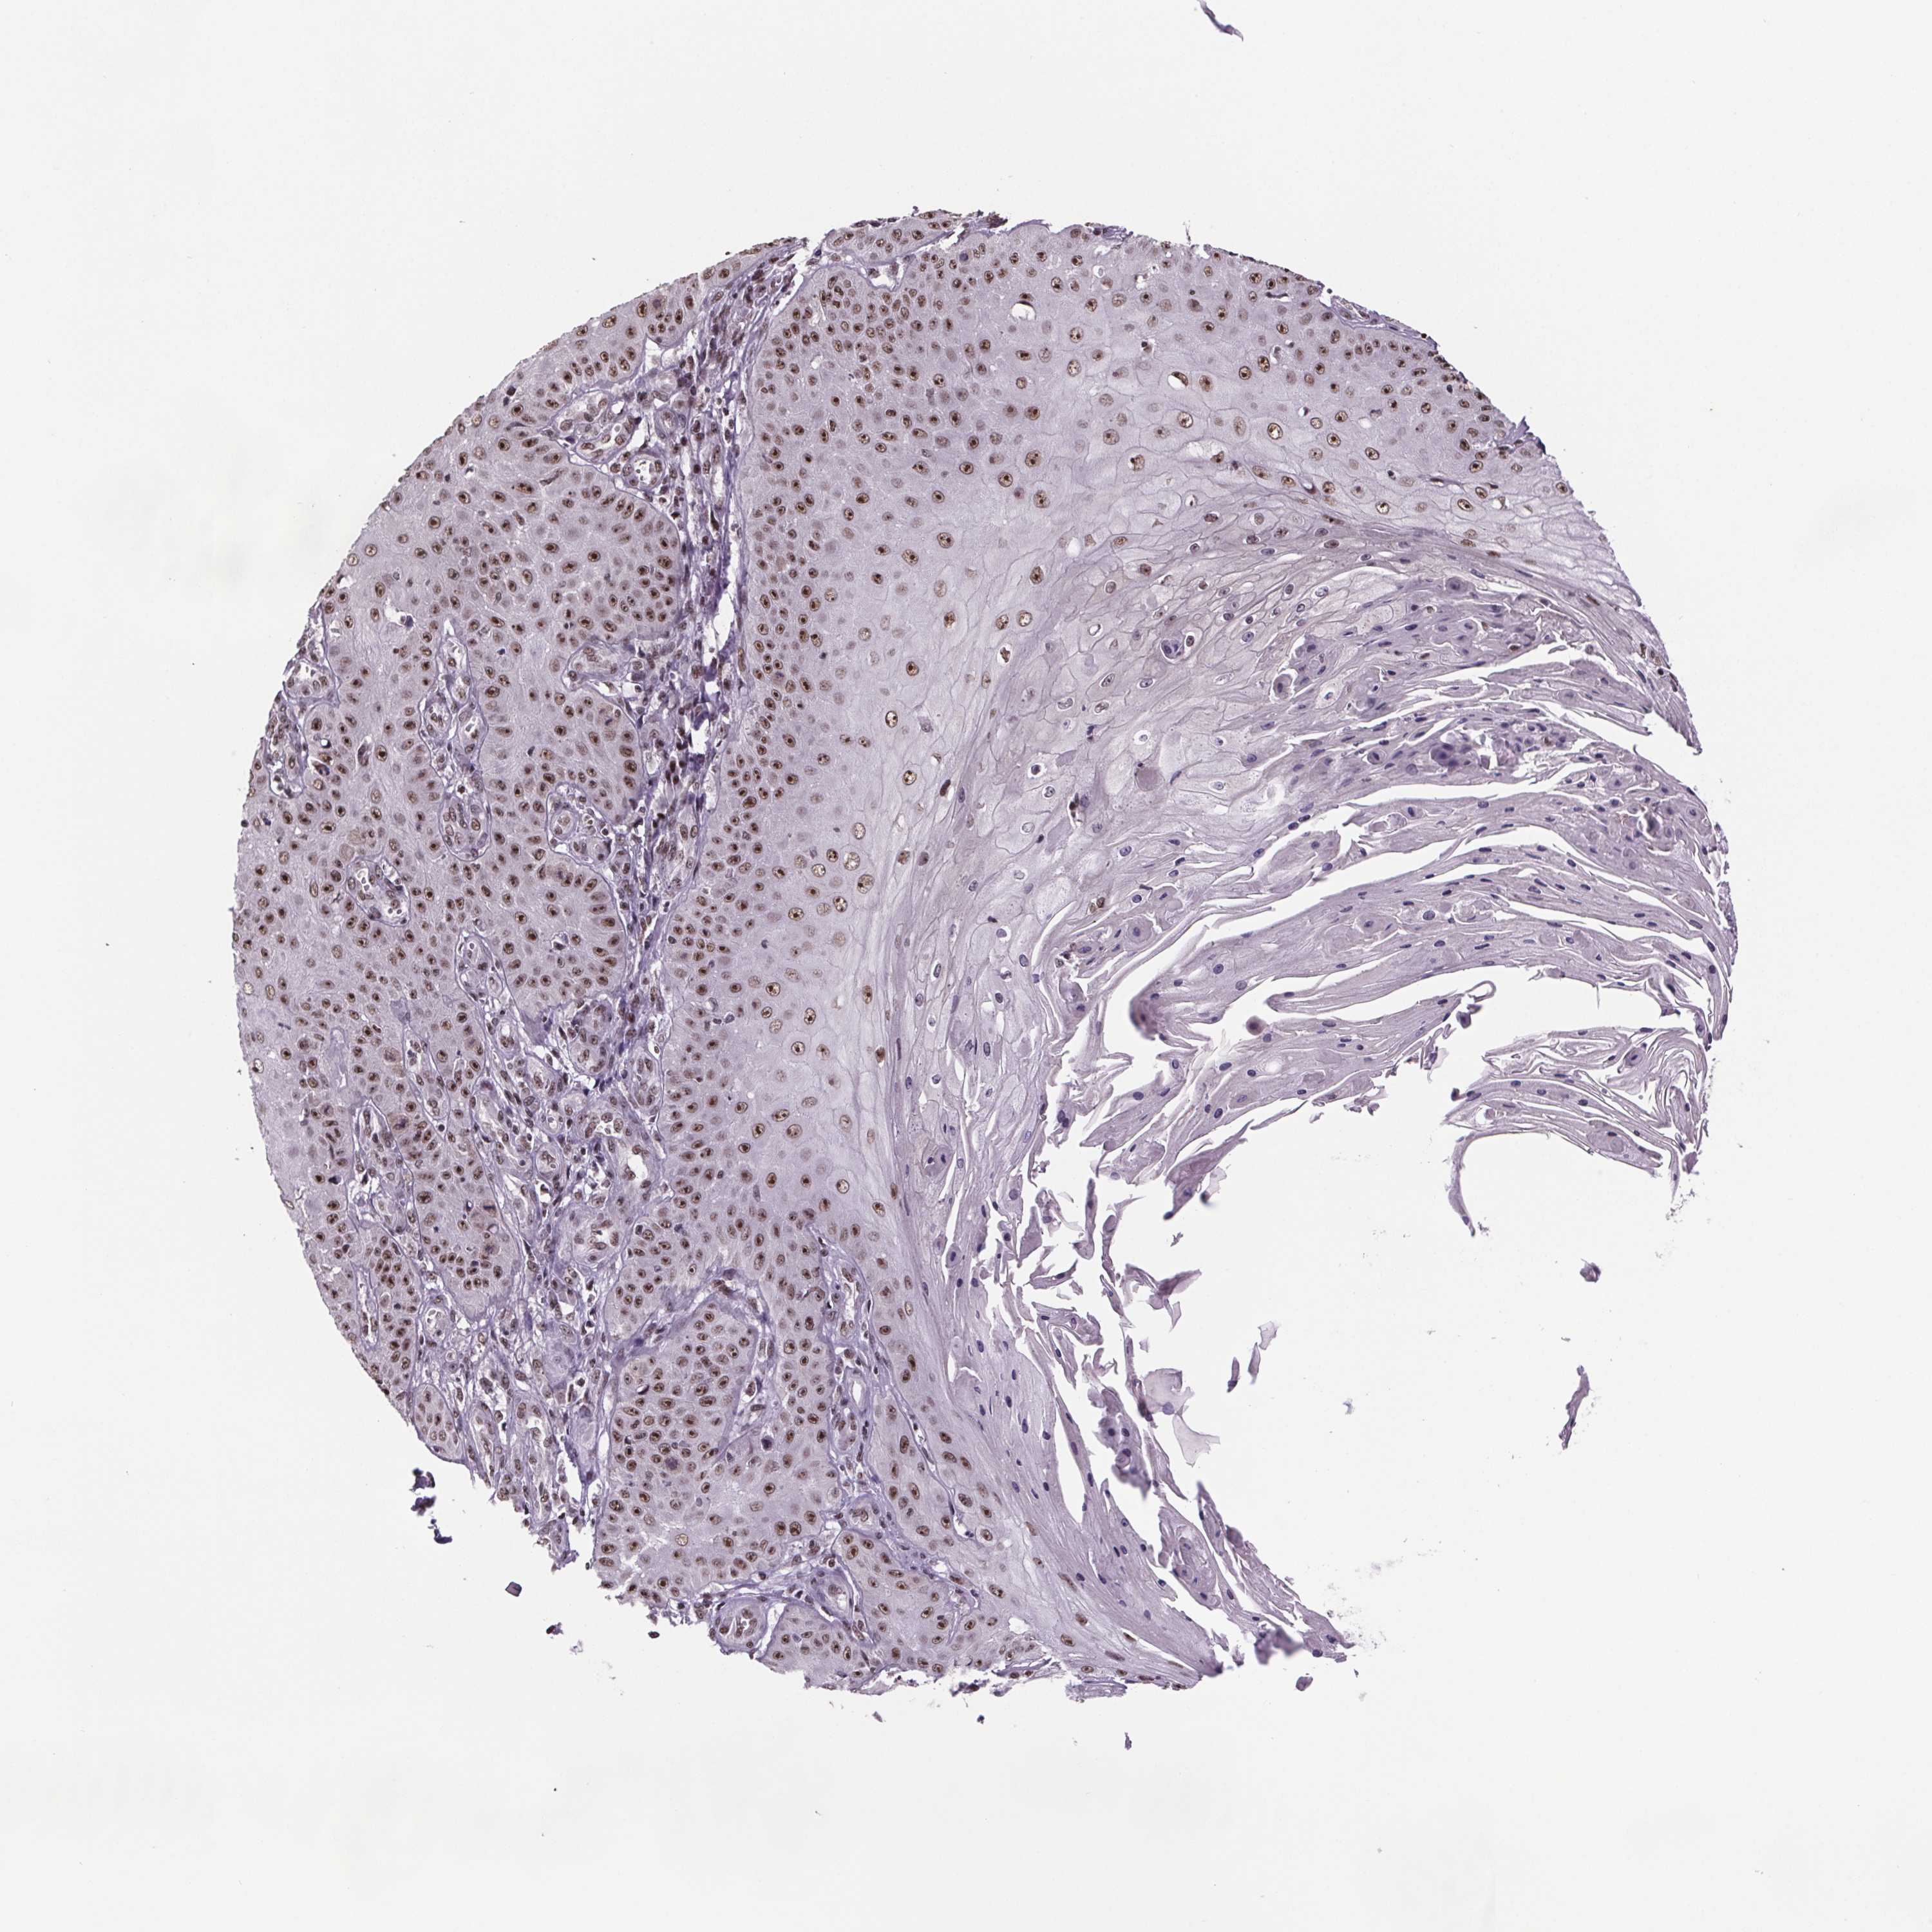

SKIN CANCER - Protein expressioni

A mouse-over function shows sample information and annotation data. Click on an image to view it in a full screen mode. Samples can be filtered based on level of antibody staining by selecting one or several of the following categories: high, medium, low and not detected. The assay and annotation is described here.

Antibody stainingi

Antibody staining in the annotated cell types in the current human tissue is reported as not detected, low, medium, or high, based on conventional immunohistochemistry profiling in selected tissues. This score is based on the combination of the staining intensity and fraction of stained cells.

Each image is clickable and will lead to virtual microscopy that enables deeper exploration of all samples and also displays staining intensity scores, fraction scores and subcellular localization as well as patient and tissue information for each sample.

Antibody HPA064930

Staining

High

Medium

Low

Not detected

Intensity

Strong

Moderate

Weak

Negative

Quantity

>75%

75%-25%

<25%

None

Location

Nuclear

Cytoplasmic/membranous

Cytoplasmic/membranous,nuclear

Basal cell carcinoma

Squamous cell carcinoma, NOS